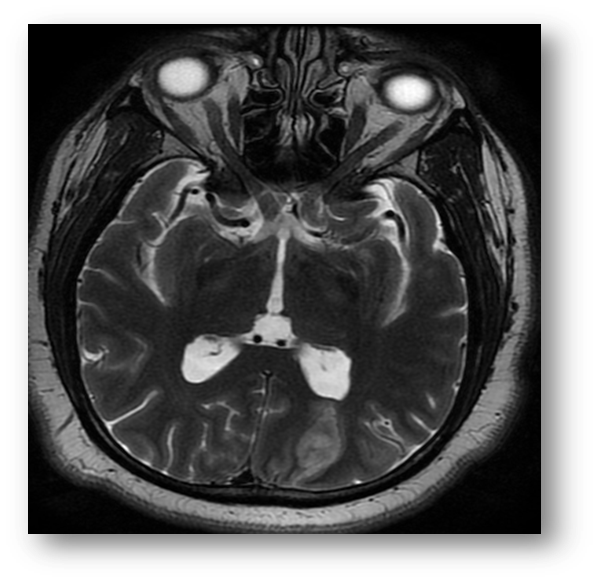

Refer to caption

Figure 3: T2 FLAIR showing hyperintense signal in the PCA and MCA distributions, consistent with acute ischemic stroke. Note that the hypointensity of cerebrospinal fluid due to fluid-attenuation allows for better contrast with the periventricular lesion.

Fluid attenuated inversion recovery (FLAIR) is useful in the diagnosis of certain pathologies such as periventricular white-matter lesion in multiple sclerosis. FLAIR can be T1 or T2 weighted. Figure (2) shows a sagittal section of a T1 FLAIR brain image, and Figure (3) shows a T2 FLAIR brain image.